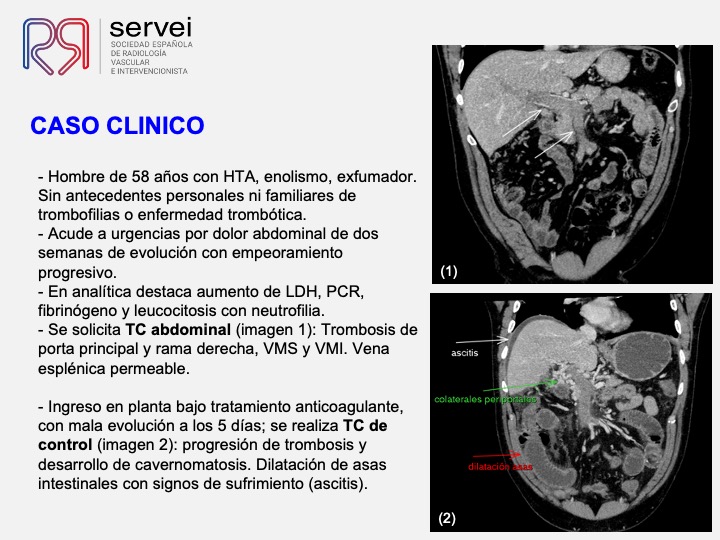

- Isquemia mesenterica venosa 02

- Isquemia mesenterica venosa 03